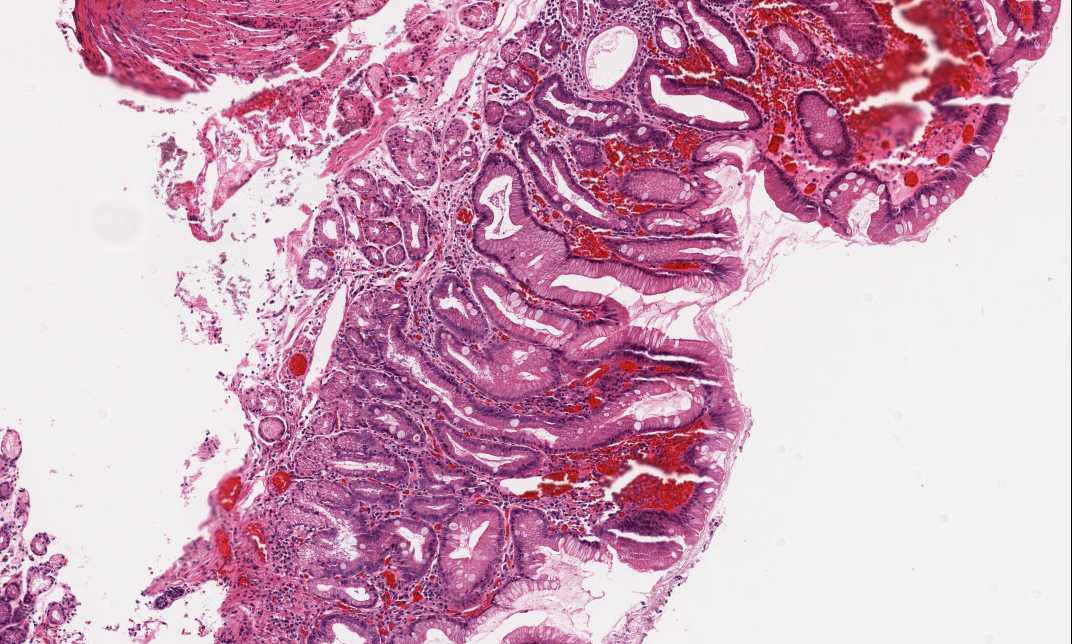

Diagnosis: Intramucosal adenocarcinoma, moderately differentiated, arising in a background of Barrett's esophagus

Area 1: In the gastric mucosa, there are some chronic inflammatory cells in the lamina propria. Many goblet cells are present here and they are quite extensive.

Area 2: Compare the area with high grade dysplasia (HD) and the normal appearing glands on the right of the image. At the interface between the Barrett's esophagus and high grade dysplasia, there are also glands with high grade dysplastic change (HD) and with goblet cell formation.

Area 3: The muscularis mucosa is not penetrated as illustrated. However, the tumor cells has already reached the smooth muscle fibers (arrow).

• In the gastric mucosa (Area 1), there is goblet cell formation (intestinal metaplasia) indicative of Barrett's esophagus.

• High grade dysplasia is present immediate adjacent to Barrett's esophagus (Area 2). Compare the differences between the architecture and the cytology between the two areas.

• The carcinoma has invaded into the lamina propria but has not penetrated the muscularis mucosa (Area 3). Therefore, this can be diagnosed as intramucosal adenocarcinoma.